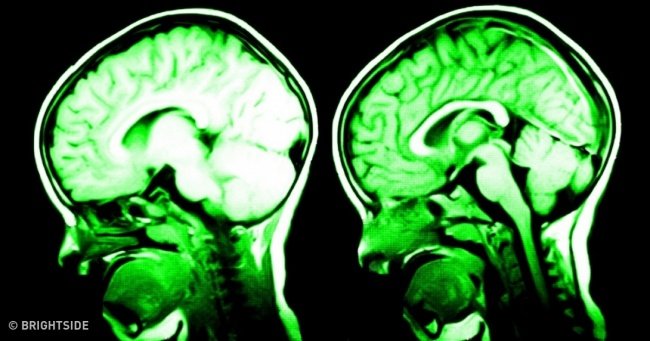

Khi mà kêu ca quá nhiều, não của chúng ta sẽ dần hình thành những suy nghĩ tiêu cực tiêu cực, luôn chỉ nhìn thấy mặt xấu của vấn đề là một trong những nguyên nhân đầu tiên dẫn đến trầm cảm.

Serotonin là chất cần thiết cho sự hoạt động vỏ não trước trán của bạn, nó kiểm soát sự phản xạ và cân bằng cảm xúc, do đó cảm giác biết ơn, thỏa mãn giúp não kiểm soát các cảm xúc hoảng loạn. Hãy nghĩ, thậm chí viết nhật ký hàng ngày về các sự kiện mang lại niềm vui hay hạnh phúc.

Các nhà khoa học khuyên rằng, bạn nên nói lên rằng bạn đang nghĩ gì, cảm thấy ra sao, bởi hành động này làm giảm hoạt động của amygdala - trung tâm sợ hãi của bộ não, và do đó làm giảm mức độ căng thẳng, và khiến bạn hạnh phúc hơn.